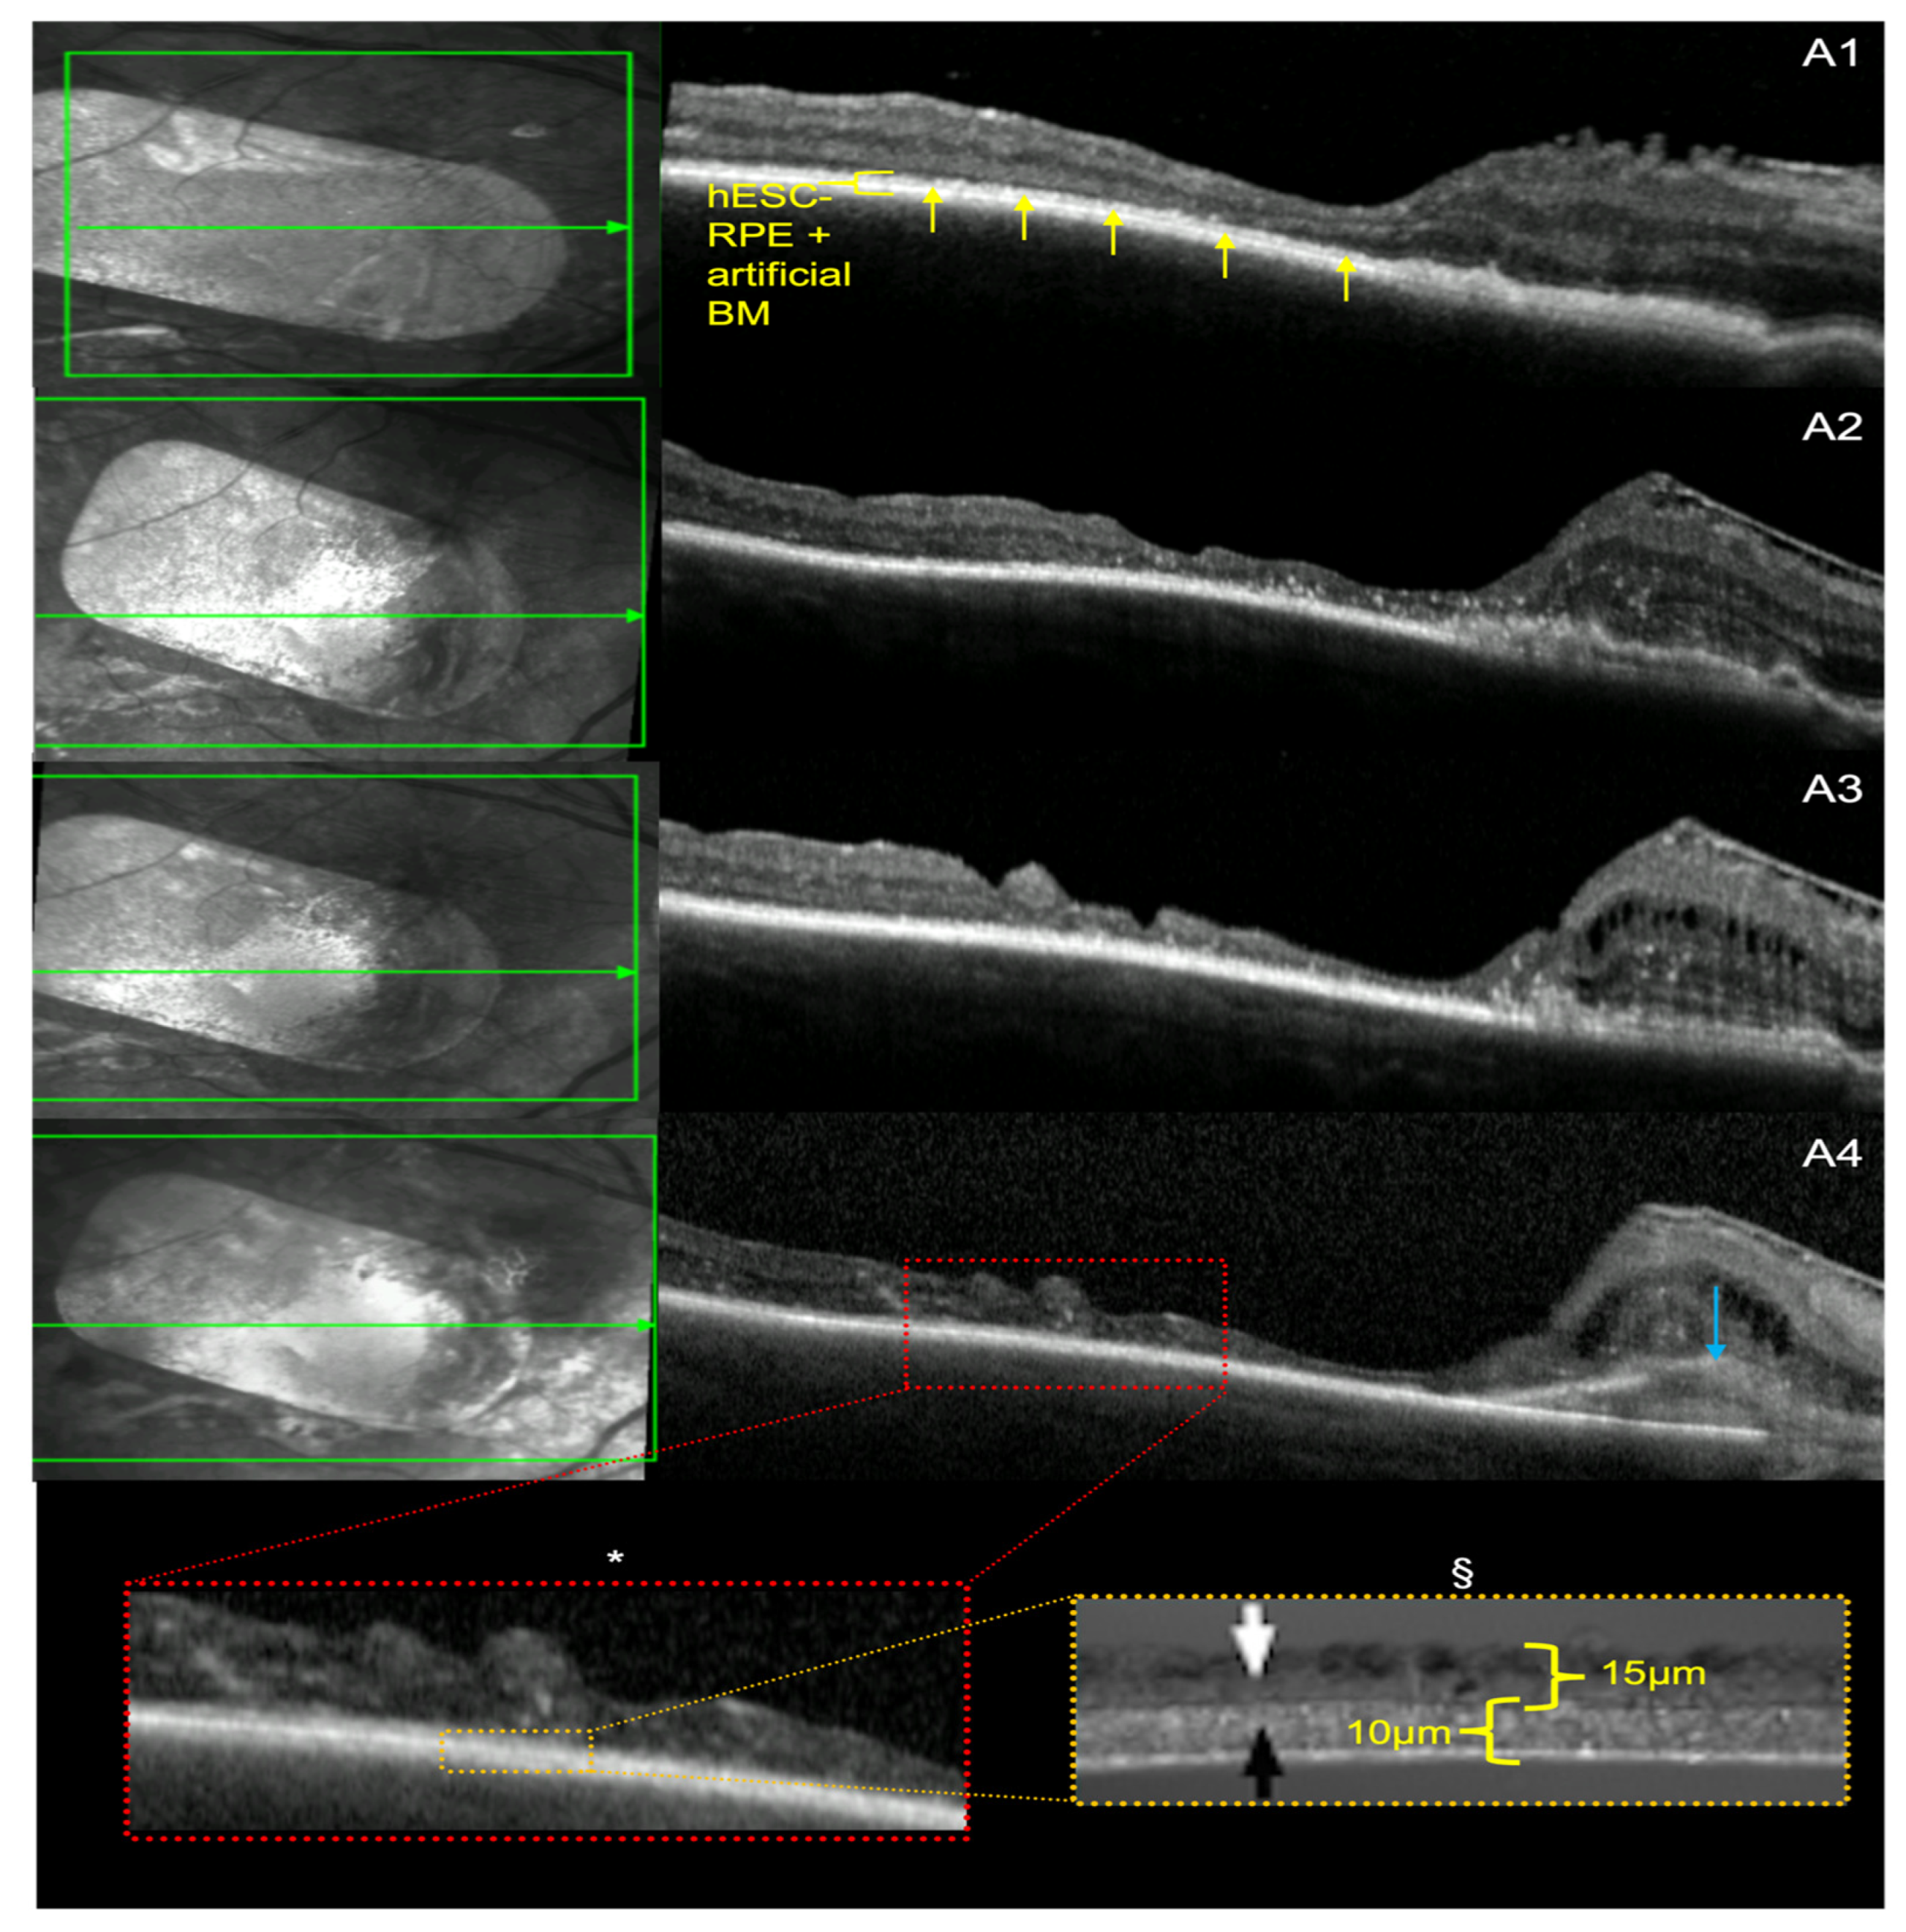

3.3. Retinal Ultrastructure

3.4. hESC-RPE and BM Thickness